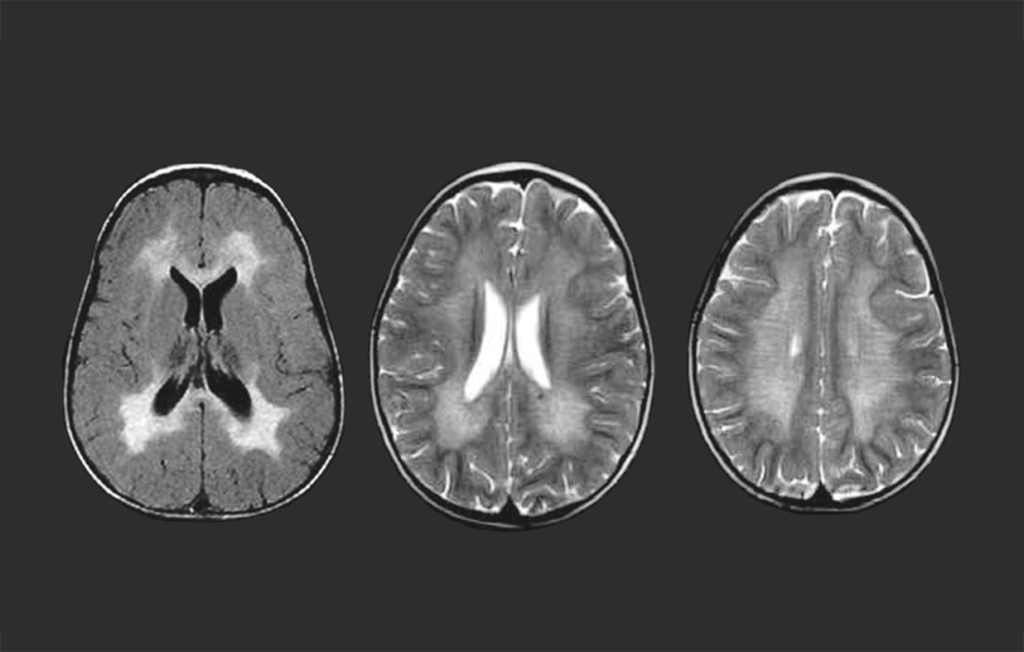

Metachromatic Leukodystrophy (MLD) is first suspected through a pattern of progressive impairment that varies by age: the late-infantile form typically begins with gait issues, such as foot drop or toe walking; the juvenile form involves a mix of motor and cognitive decline; and the adult form often manifests as behavioral changes or slurred speech. To confirm a diagnosis, clinicians use a combination of genetic testing for ARSA and PSAP mutations and biochemical testing to measure sulfatase activity and urinary sulfatide excretion. While brain MRIs are essential for identifying the signature pattern of myelin loss and tracking brain injury over time, it is critical to note that early imaging in young children can sometimes appear normal.